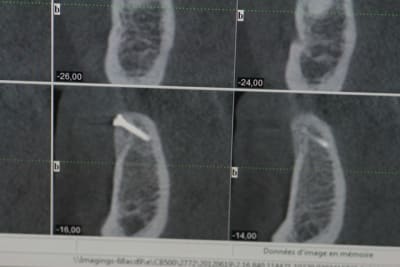

Pour se faire une meilleure idée de ton boulot, ce serait bien d'avoir qq coupes pour avoir une meilleure idée de l'objectif de cette ROG.

voilà pour compléter...

pano et les coupes pour les 2 futurs implants...

ce qui me posait problème, c'est l'inclinaison et la forme de la branche horizontale dans cette zone rendant l'implantation simultanée extrêmement délicate...pour ne pas dire risquée...

Comme quoi la pano veux rien dire ! La forme de la crête est môche !